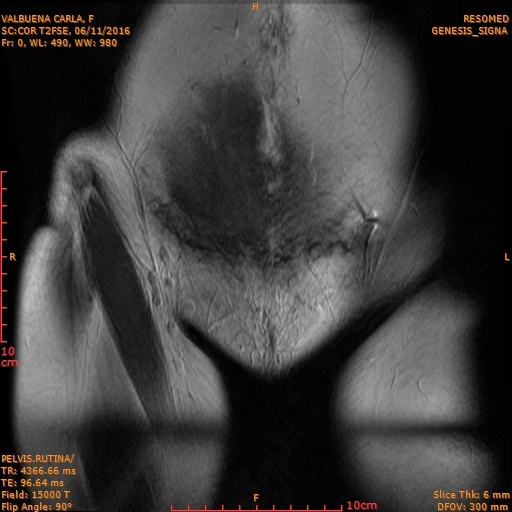

During my annual routine check-ups, in order to be ready to search for our second baby, precisely on the day that I was doing my breast ultrasound (because I was still breastfeeding my daughter), I asked my colleague to check my uterus with the ultrasound equipment. An image appeared and the doctor asked to evaluate it with an MRI. To our surprise, the results confirmed that I had a tumor and had to have an immediate surgery.

Therefore, on Tuesday November 22, 2016 I had to undergo surgery, and that day God changed my life plans. The doctors had to practice a hysterectomy, take out my ovaries, the uterus. They had to remove part of my intestine and my appendix as well, due to the fact that the biopsy showed that it was a leiomyosarcoma with metastasis. These were days of great anguish and worry, while we awaited the results of the definitive biopsy, both for myself and my family, as a doctor I understood how risky my situation was.

I definitely consider that God has given me a second chance, due to the fact that I had surgery on time, which is not frequent with this type of tumors. Usually they are not surgical. They usually have a large size and when people go see their doctors, and  it is mainly for secondary reasons related to the tumor. In my case it measured 10 cm, which is a small measure for this type of cancer. However it proved to be aggressive, since it presented metastasis all around.